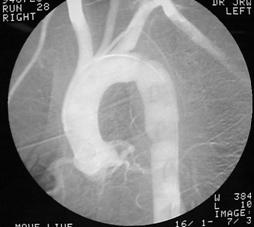

Corp ascutit penetrat in regiunea precordiala Mediastin largit

Aortograma  Mediastin largit

Leziune la nivelul istmului aortic

Aortograma.Leziune

situata distal de  Aorta

clampata

emergenta arterei subclavii stangi Segment

lezat excizat